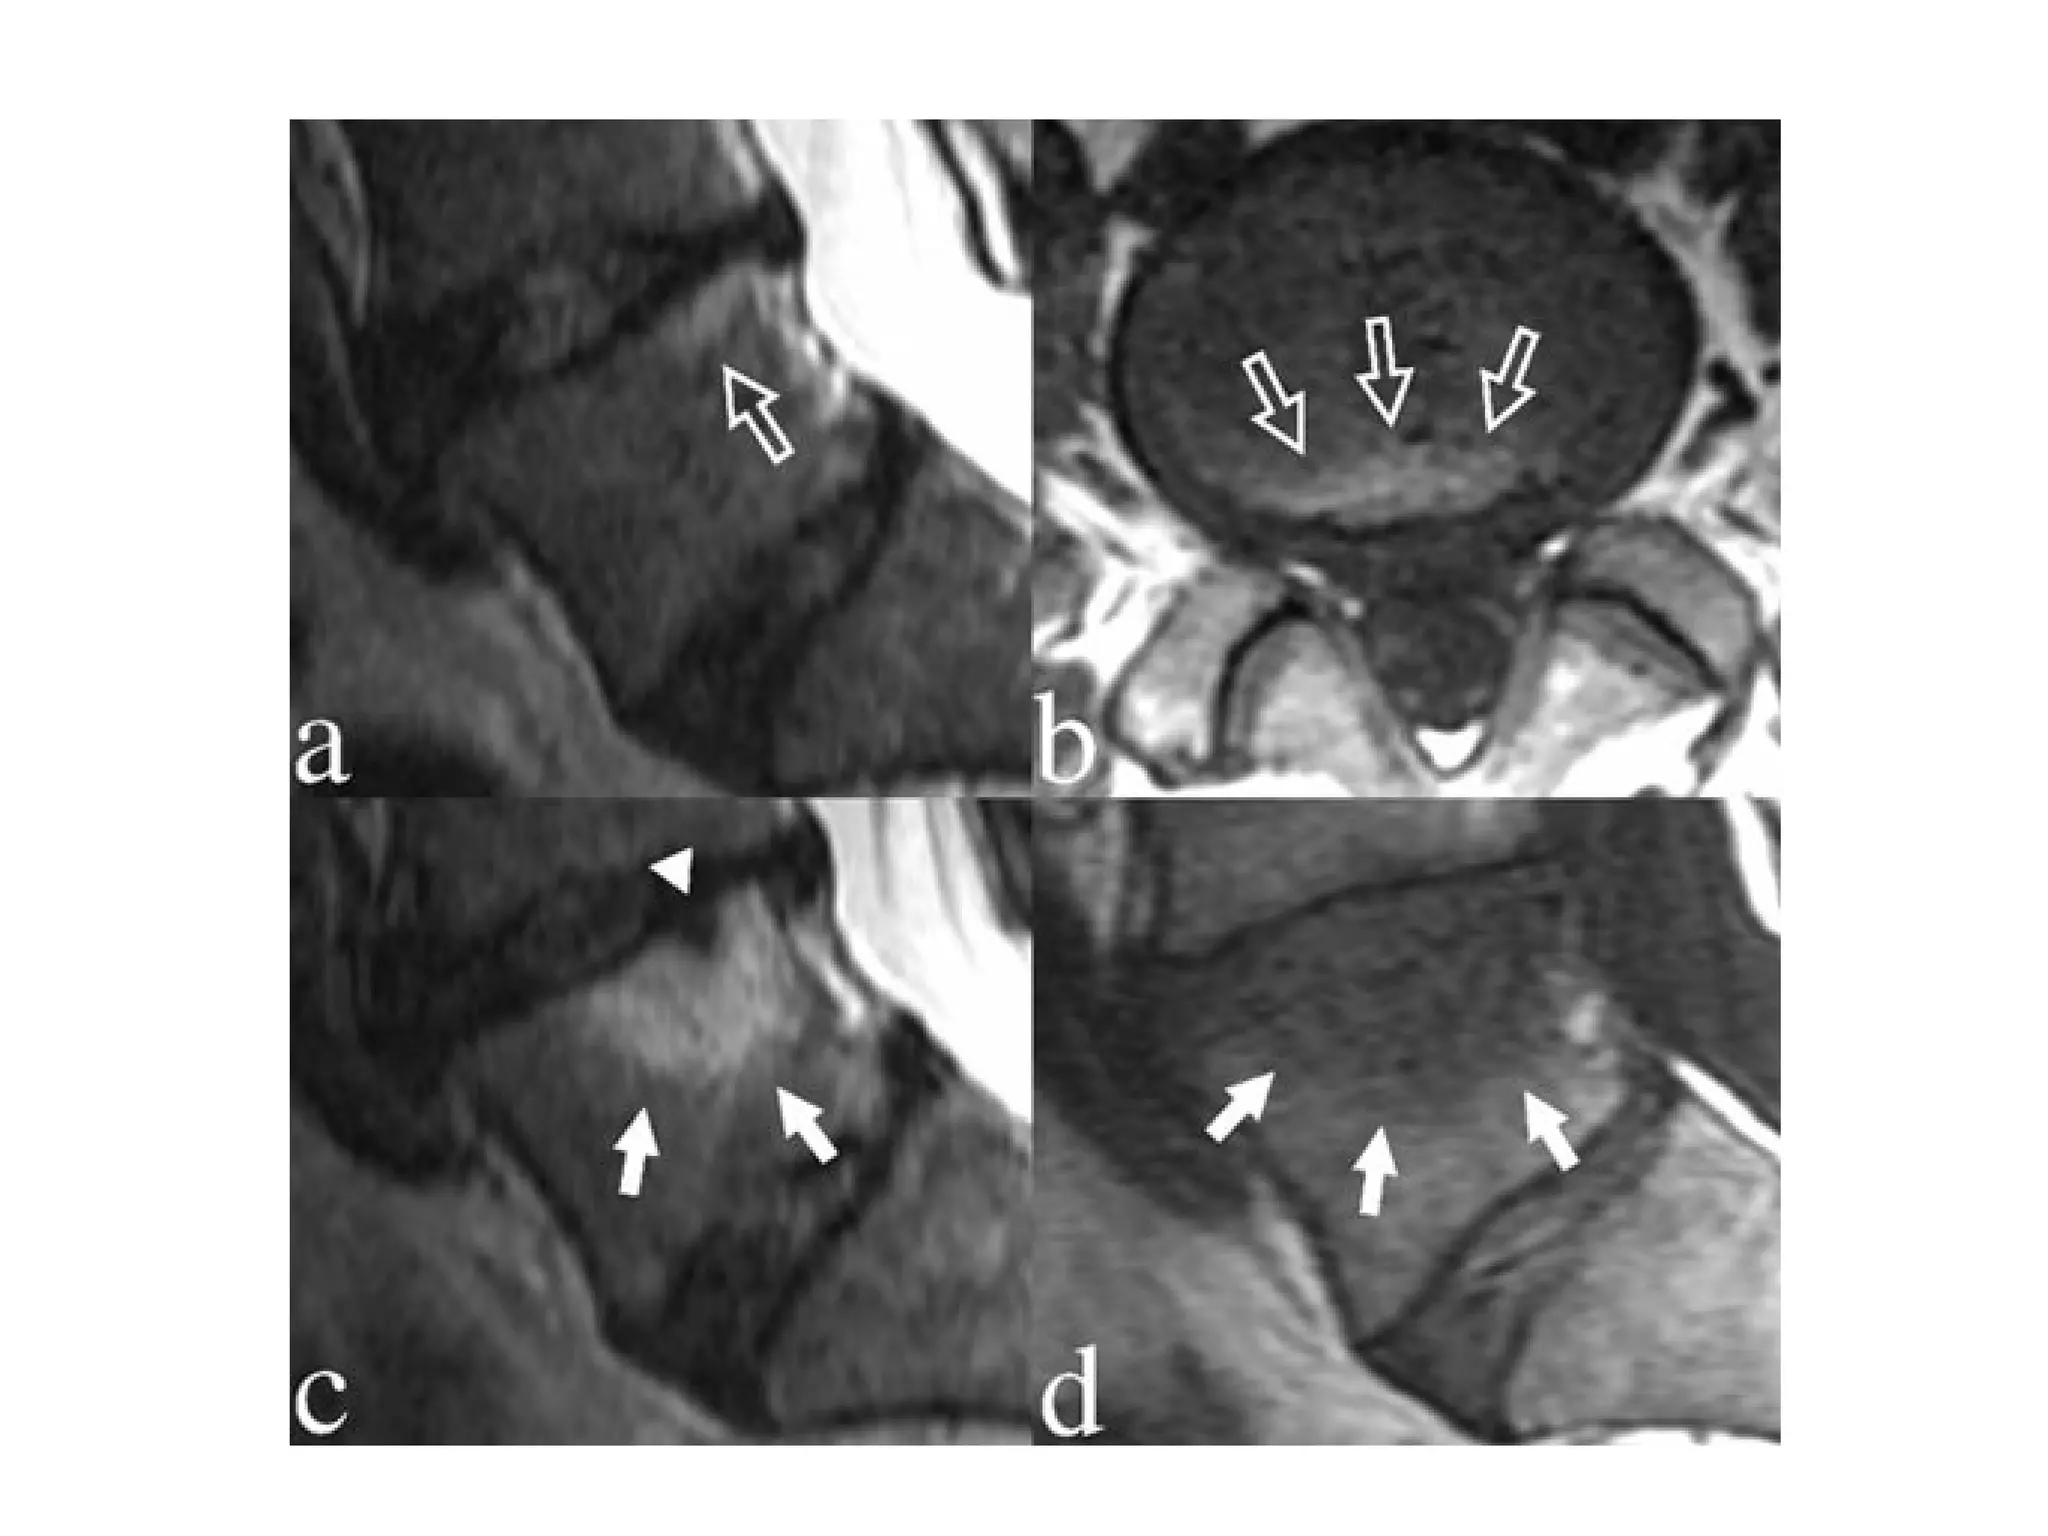

Modic type 1 deg. changes (MI)

Hypointense on T1WI (A)

Hyperintense on T2WI (B)

Modic changes

type 1 in

lower endplate

of L4

and

upper endplate

of L5

Modic Type I (Edema)

Modic type 2 degenerative

changes (MII)

hyperintense on T1WI (A)

isointense or slightly hyperintense on T2WI (B)

type 2 in the

the upper

endplate of S1

Modic type 3 degenerative changes

(MIII)

Hypointense on both

T1WI (A) and T2WI (B)